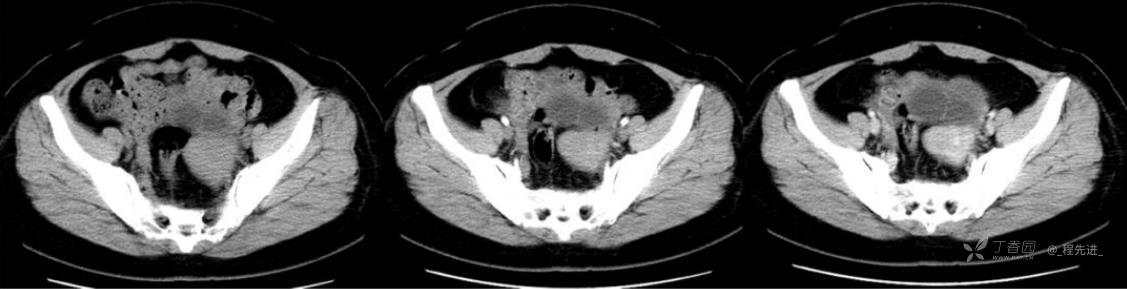

1月特别精彩病例|中老年女性,盆腔包块近半年持续增大【病理已公布】

患者年龄:53岁

简要病史:4年前体检时发现盆腔包块及子宫肌瘤,近半年复查盆腔彩超发现包块持续增大,近1年月经欠规律,伴腰、腹胀。

体格检查:宫颈举痛(+),子宫增大,质地中等,活动可,无压痛;右下腹轻压痛,无反跳痛,左侧附件区未扪及明显包块,无压痛。

阴式彩超:子宫约65*58*44mm大小,子宫肌层可见多个低回声块影,较大的为35*27mm(位于子宫前壁下段偏右侧壁),边界清,内回声欠均匀,后方回声衰减。考虑子宫多发肌瘤。子宫后壁可见一混合回声包块,大小约31*20mm,边界不清,内呈强弱回声,分布不均,考虑子宫腺肌瘤,其他疾患待删。子宫内膜厚6mm,宫颈可见多个囊性暗区,边界清,内透声好,后壁效应增强,较大的为15*11mm。子宫前方偏左侧可探及一大小89*75mm囊性肿块,边界清,壁薄光滑,内透声好,可见分隔光带